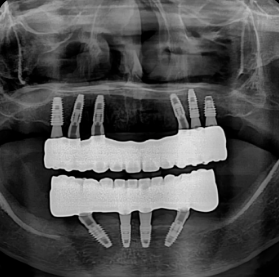

ALL IMPLANT VS FULLARCH

전체임플란트 vs 풀아치

나에게 꼭 맞는 치료법은?

“저도 풀아치를 할 수 있을까요?” 무조건 풀아치를 권하지 않습니다.

환자분께 가장 좋은 치료가 저희에게도 가장 좋은 치료이기 때문입니다.

풀아치가 필요한 경우

틀니를 오래 사용하셨거나, 잇몸뼈가 전반적으로

많이 내려앉아 치아만 만들 경우

너무 깊이 보이는 분들에게 가장 이상적입니다.

전체 임플란트가 더 나은 경우

치아를 뺄 지 않아도 잇몸뼈가 충분히 남아있는 분들은

잇몸 뼈를 삭제할 필요 없이, 치아만 만드는

전체 임플란트가 더 적합할 수 있습니다.

한눈에 보는 치료법 비교

특징 디지털 풀아치 전체 임플란트 전통 틀니

씹는 힘 우수 (자연치 80%) 최우수 (90~100%) 미흡 (20~30%)

뼈 이식 거의 불필요 필요한 경우 많음 해당 없음

편안함 고정식, 이물감 없음 고정식, 내 치아 같음 탈착식, 이물감 있음

치료 기간 단기간 (약 2~3개월) 장기(6개월~1년) 비교적 빠름

장기 안정성 매우 높음 (10년 후 93% 이상) 매우 높음 재제작 필요 (5~7년 주기)

전체 비용 높음 매우 높음 낮음(중)